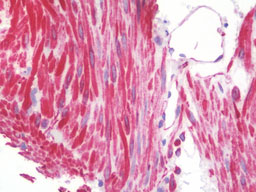

Anti-DES / Desmin antibody IHC staining of human small intestine. |